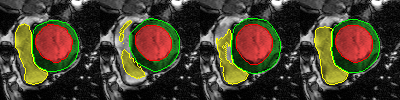

Careful inspection reveal that errors are not uniformly distributed. Interestingly, conv-deconv and U-Net produce accurate results on most slices of each 3D volume as illustrated in the first two rows of Fig. 2. That said, they often get to generate a distorted result for 1 or 2 slices (out of 7 to 17) which end up decreasing the Dice score and increasing the Hausdorff distance. This situation is shown in rows 3,4, and 5 of Fig. 2. Overall, the right ventricle is the most challenging region for all three methods. It is especially true at the base of the heart, next to the mitral valve where the RV is connected to the pulmonary artery. This is illustrated in the last row of Fig. 2.